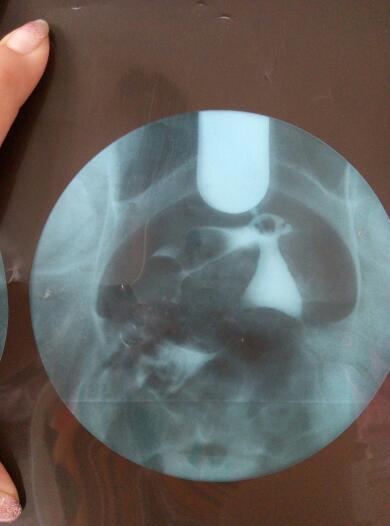

帮我看看,什么情况,还能自然受孕吗?不做手术吃药能解决吗?好人一生平安 点击展开 匿名用户 2016-06-01 09:40 满意回答 根据你的输卵管造影检丛遮查结果显示,筝扬露应该考虑是属于输卵管阻塞等原因引起的症且脑状,应该是比较难自然受孕的,应该积极进行治疗。可以考虑进行输卵管通水治疗的。必要时可以考虑进行宫腔镜,三镜一丝等手术治疗。 太阳荣华医师 2016-06-01 10:03 宝宝知道提示您:回答为网友贡献,仅供参考。 相关问题 请问这是什么?好人一生平安帮我看看吧 朋友们懂得人帮我看看,像这样的报告我想做人工受孕的机率大吗? 一个朋友结婚四年多了,他老婆不孕 现在医院要她做手术治疗 先吃了催排药打算现让他们试一个月自然受孕